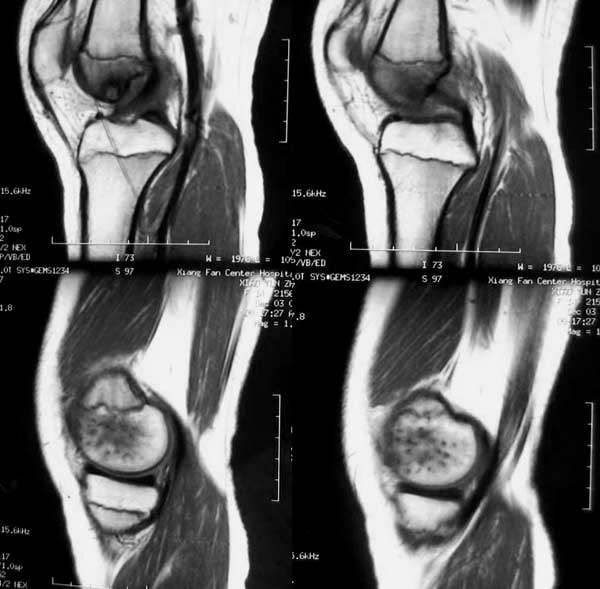

14岁女孩,7月前右膝关节疼痛,进行性加重,无外伤,无潮热盗汗,无高热,未治疗。1周前入院,下肢皮肤牵引,抗炎治疗,症状减轻。入院查右膝关节轻肿,浮膑(-),碱性磷酸酶140,余(—)。如何诊治?1周前ct 见关节面破裂,关节腔穿刺少量血性液:细胞学检查示滑膜炎改变,培养未见细菌生长。 7月前ct

6月前mri,1周前ct

病变特点:股骨的非负重区的破坏病灶,是结核的特点,病灶边沿的硬化又是细菌性感染的特点,建议检查一下肺部有无结核。

考虑结核可能性大,骨样骨瘤待排;结核单关节病变好发于承重关节,髋关节、膝关节病变占80%左右,关节局部疼痛、肿胀,活动受限,起病缓慢。骨样骨瘤多发生在长骨的骨皮质,很少部分发生在骨松质,以股骨、胫骨最常见,病灶周围有显著的反应性硬化环,局部疼痛,夜间较重,近关节的病灶有关节积液。本病例应进一步做其他检查。

低毒感染,骨样骨瘤待排,mri表现整个骨够信号异常并跨够线,良性肿瘤基本排除,(但骨样骨瘤与骨母与感染有关),病灶周边硬化不是tb表现。

病变骨质增生硬化,不支持结核。mri示病变中心内短t1、长t2信号,考虑为骨样骨瘤并瘤巢内出血。

病变特点:股骨的非负重区的破坏病灶,病灶边沿的硬化明显,ct mri均显示病变为慢性过程,关节积液不明显,考虑低毒感染可能性大,请继续抗炎治疗,不除外骨样骨瘤

病变特点:病灶较小,周围硬化环厚/明显,中心ct呈透光区,mr可见液性成分;14岁小孩,骺端关节面的病变,可考虑的病变有:1/低毒力感染,嗜酸性肉呀肿,2/软骨母细胞瘤,年龄/好发部位/信号/密度均可符合诊断,唯一不支持的是病灶中心未见点状钙化或骨化影3/腱鞘囊肿4/巨细胞瘤和骨囊肿可以不考虑。

骨骺轻度水肿,近髁间凹关节面侧骨局灶性破坏,病灶边缘有较多的环形硬化,骨显著硬化是细菌性感染的特点,关节积液不明显...抗炎治疗症状减轻,考虑为低毒感染可能性大(brodie骨脓肿可能).请继续抗炎治疗